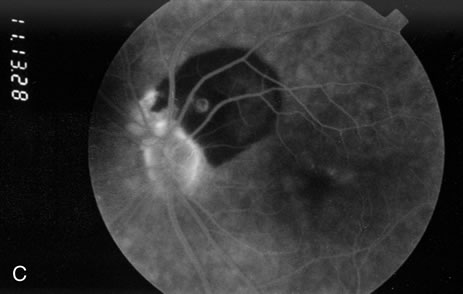

Fig. 2. A. Color fundus photograph of a 200-micron macroaneurysm that arises from a retinal artery near the optic disc with thin subretinal hemorrhage that does not threaten the fovea. B. The midphase fluorescein angiogram reveals blockage of choroidal but not retinal vascular hyperfluorescence. C. The late-phase angiogram demonstrates staining of the macroaneurysm.[pa[et[ol0]